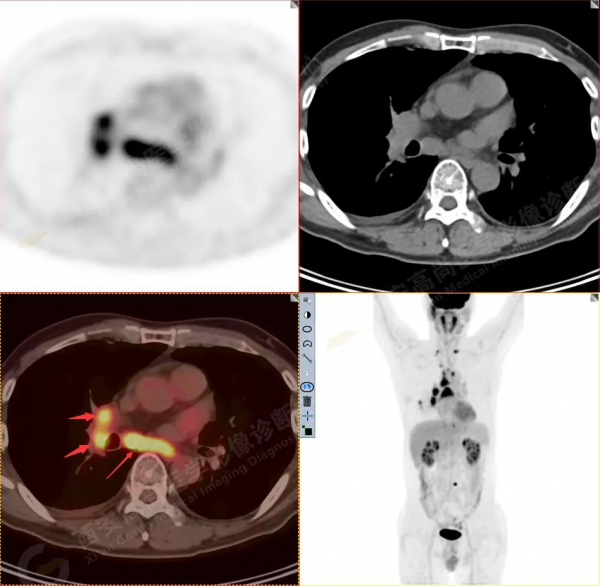

1.以下為肺內原發灶

1.右肺下葉後基底段軟組織結節(約1.5cm×1.2cm),與相鄰後胸膜分界不清,呈FDG代謝異常增高,結合病理,符合肺腺癌伴鄰近胸膜侵犯。

3.右側肺門、縱隔(1L、1R、3A、4、6、7組)及雙側鎖骨上多發腫大淋巴結,呈不同程度FDG代謝異常增高,考慮為淋巴結轉移。